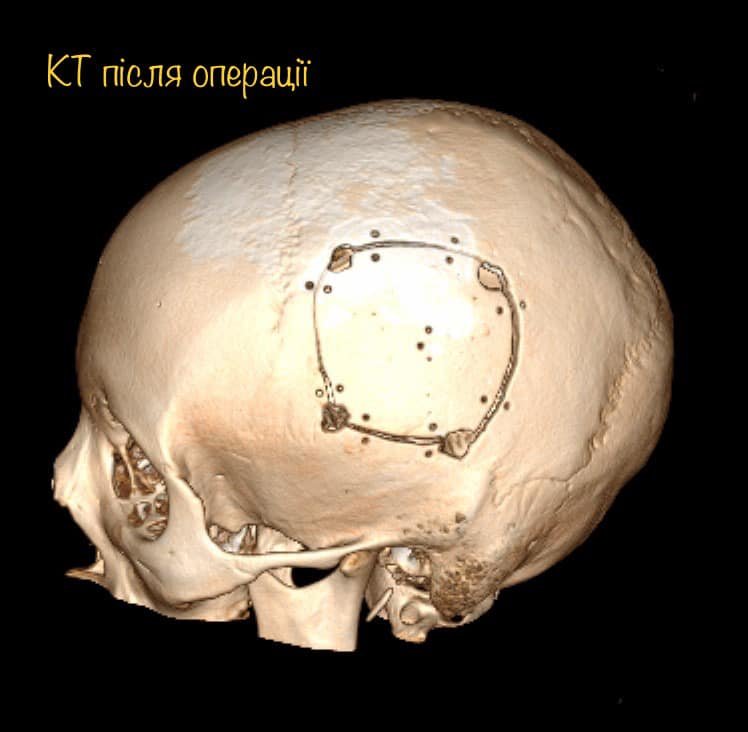

На МРТ виявили пухлину головного мозку з крововиливом в лівій домінуючій (важливішій) півкулі, в якій, власне, окрім центрів, які рухають кінцівками однієї половини тіла, розташований дуже важливий центр мови.